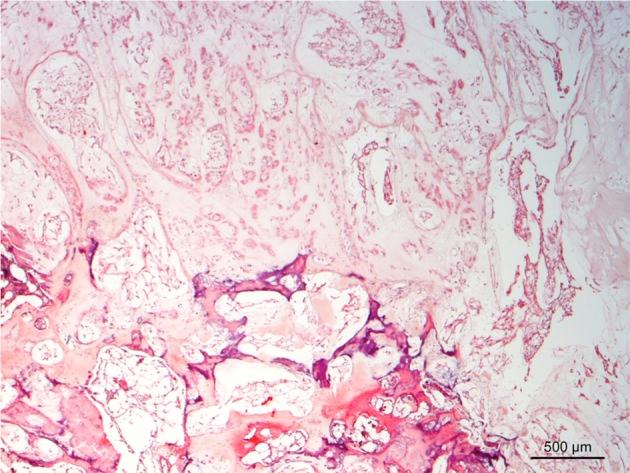

A Bengal tiger was presented for evaluation of weakness, ataxia and inappetance. Computed tomography (CT) and magnetic resonance imaging (MRI) revealed a mass extending from the T7-8 vertebral body to the left rib and compressing the spinal cord. On CT, the bone destruction and sequestrum were shown. On MRI, the multilobulated mass appeared hypo- to isointense in T1-weighted and hyperintense in T2-weighted images. The tiger died after imaging, most likely from renal failure. Chordoma without metastasis was diagnosed on necropsy. The imaging characteristics were similar to those found in chordoma in humans. This report describes the use of CT and MRI in an exotic species.

一只孟加拉虎因虚弱、共济失调和食欲不振前来接受评估。计算机断层扫描(CT)和磁共振成像(MRI)显示一个肿块从T7 - 8椎体延伸至左肋骨并压迫脊髓。在CT上,显示出骨质破坏和死骨。在MRI上,多叶状肿块在T1加权像上呈低至等信号,在T2加权像上呈高信号。这只老虎在成像检查后死亡,最有可能死于肾衰竭。尸检诊断为无转移的脊索瘤。其影像学特征与人类脊索瘤相似。本报告描述了CT和MRI在一个外来物种中的应用。